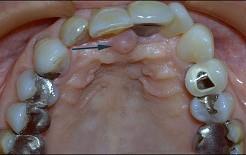

无牙颌患者的口内特征为 ( )

无牙颌患者的口内特征为 ( )![]()

A牙列缺失